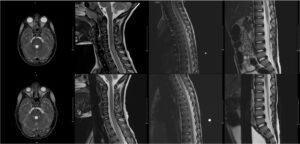

Mycoplasma Associated Acute Transverse Myelitis. MRI. Unannotated. JETem 2025